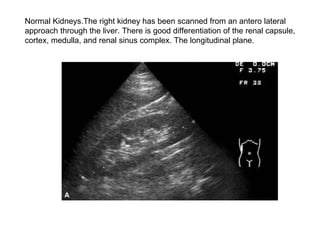

Normal Kidneys.The right kidney has been scanned from an antero lateral  approach through the liver. There is good differentiation of the renal capsule, cortex, medulla, and renal sinus complex. The longitudinal plane.